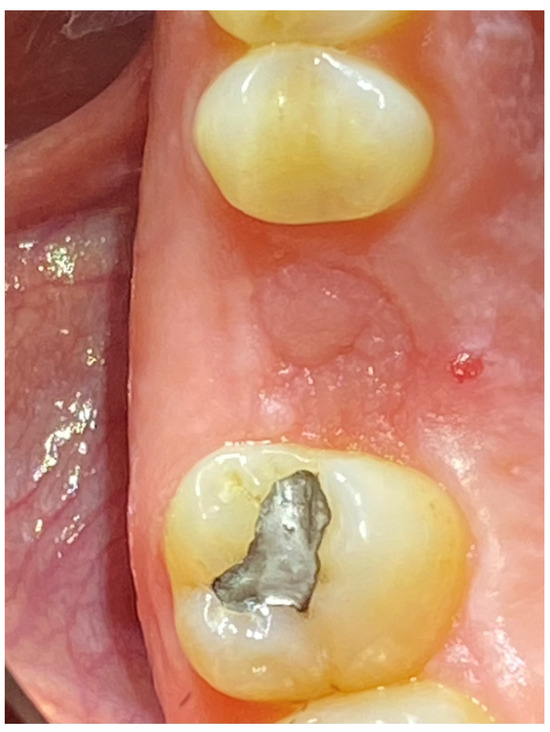

2.6. Case Presentation. Nano-HA Applied to Socket Preservation Procedures

3. Results